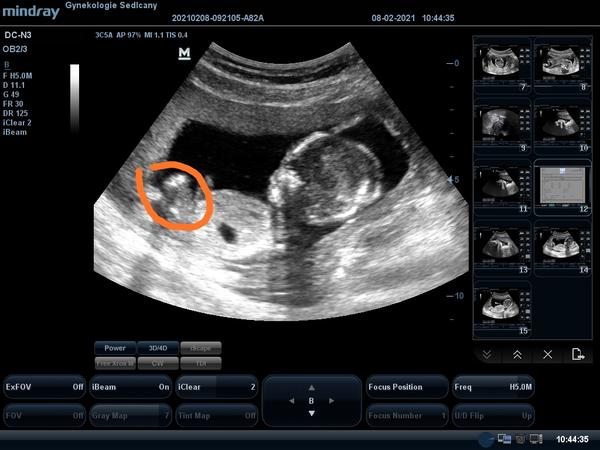

Z tyhke fotky se to poznat neda, i kdyby se tady nasel nejaky odbornik na ultrazvuky.. Neni videt mezi nohy. Po 20 tydnu uz maji kluci vyvynuty pindik, ktery uz je jasne videt. Tak jestli ho doktorka neviděla, tak to bude asi holka.

@nagojka No takhle z boku nejde pres nozicky videt. A kdyz se k tomu nevyjadril doktor, tak tady to taky asi nikdo nepozna... Z jakeho tydne je fotka?

Jestli je to z prvniho screeningu, tak tam se pohlavi urcuje podle pohlavniho hrbolku, kavove zrno videt jeste nejde.

To by musel byt pohled zespodu na pohlavi.